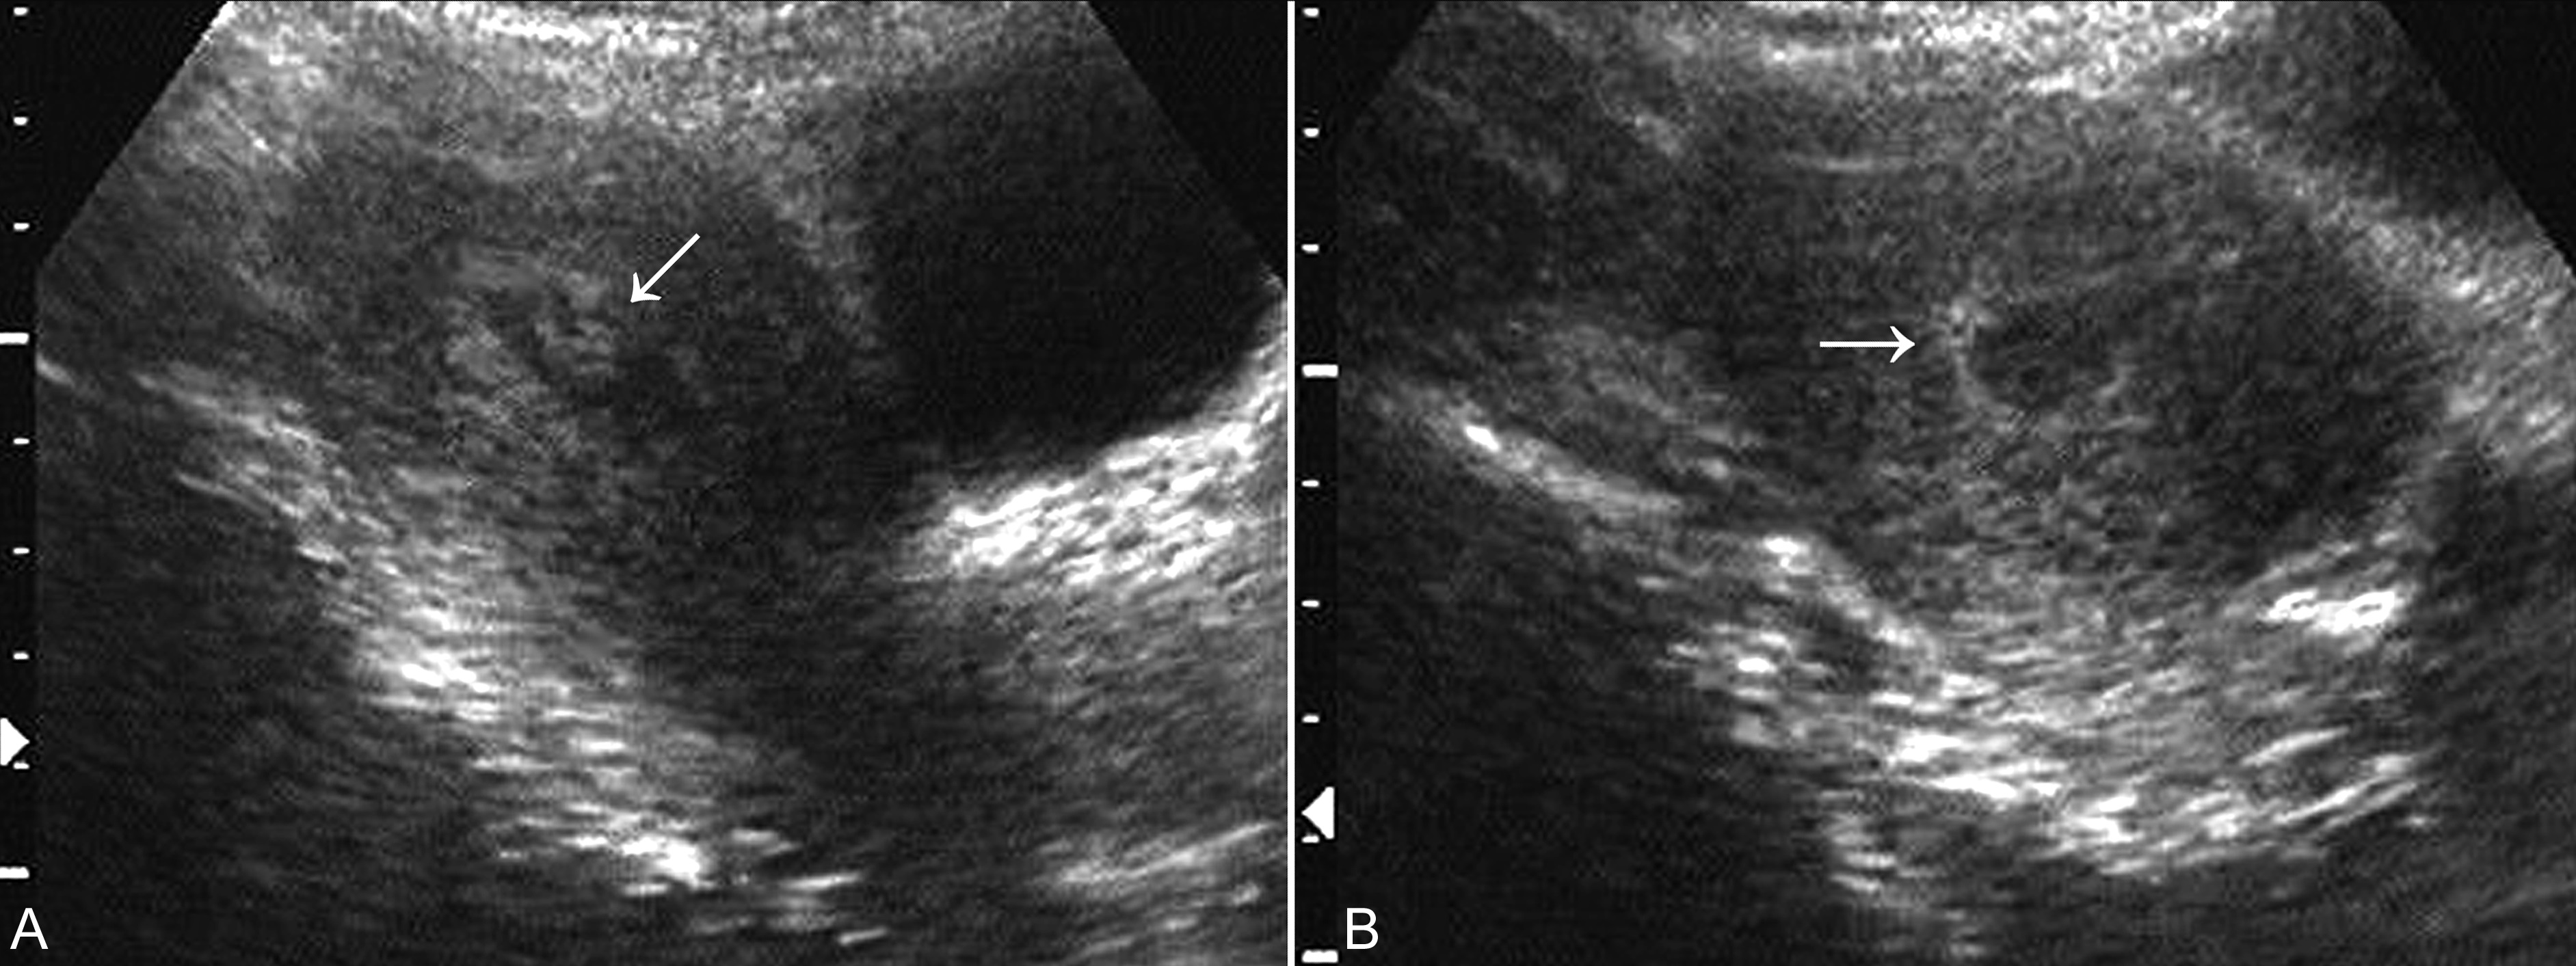

妊娠囊大小正常或较正常缩小,位置下移、变形(图3A)、边缘失去连续性;内部胚胎或胎儿活动消失,心脏搏动明显变弱或不规律、或消失(图3B);如果绒毛膜下血肿超过15ml以上并波及胎盘基底部,即便没有孕囊移位和胚胎死亡,多数也将以流产结束妊娠。

图3 难免流产声象图:变形的孕囊(GS)

子宫小于停经月份,妊娠囊消失,宫腔内残存不规则无回声区或低回声区,分布不均匀(图4),或可见死亡的胚胎或胎儿回声,或可显示胎儿的骨骼强回声。结合病史可作出不全流产的诊断。

图4 不全流产声象图:胎体已排除,箭头指示宫腔内及宫颈管处仍有胚胎残留物